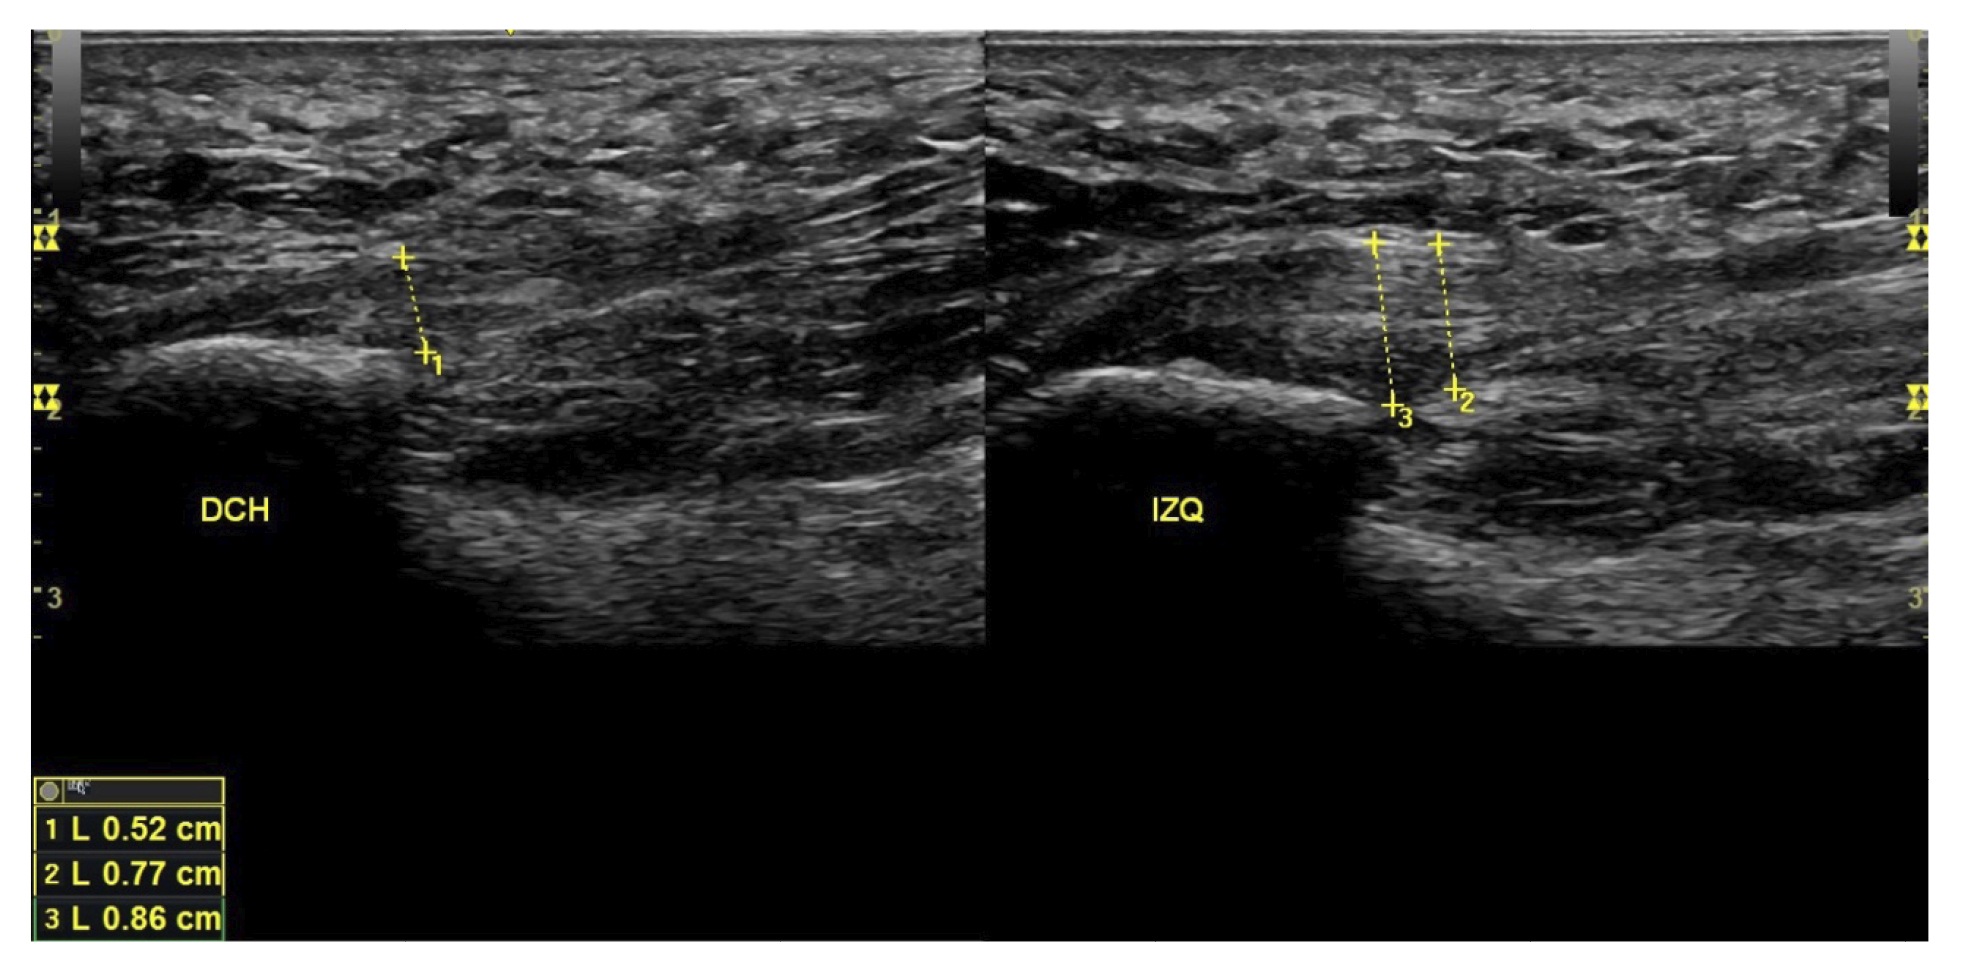

All patients underwent a clinical evaluation and an ultrasound evaluation. The clinical evaluation was based on a visual analog scale (VAS) (13) (0-10) and the Foot Function Index (FFI) (14,15), which assesses function on a scale of 0 to 100. Subjects were also classified as sedentary, active, or athletes based on their daily physical activity, as well as whether it was the first time the disease appeared, a recurrence, or chronic(16). Sex, weight, and height were also evaluated, as well as the presence of vascularization in the plantar fascia visualized with ultrasound at the time of the initial evaluation and the biconvex17 or flattened shape of the plantar fascia (Figure 1).

Figure 1. Plantar fascia with normal morphology on the left and biconvex plantar fascia on the right.

All patients had experienced the classic symptoms of PF, including pain when taking the first steps after waking up or after sitting for a long time. Patients felt pain upon palpation of the proximal plantar fascia and reported that the pain worsened as the day progressed. The diagnosis was established based on symptoms and confirmed by ultrasound using high-resolution equipment (Alpinion Ecube 9, ALPINION MEDICAL SYSTEMS Co., Ltd., Republic of Korea) with a 6-12 MHz linear transducer (Figures 2 and 3).

Figure 3. Area of measurement of plantar fascia thickness. The dotted line corresponds to the thickness measurement.